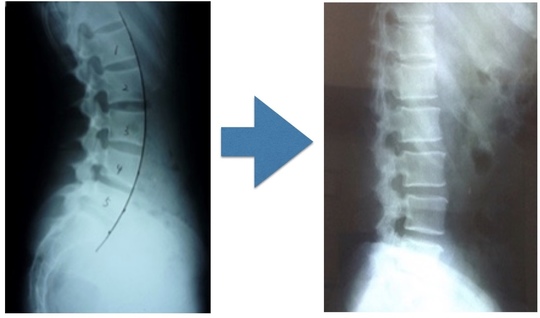

腰痛の問題解決には関節の動きを作る

痛みを繰り返すと関節は可動域を失います。

痛みを繰り返すと、筋肉は硬くなりますし、関節の動きも制限します。いわゆる、『関節拘縮』というものです。

これと同じことが腰椎の中でも起きてきます。

しかし、すべての関節がかたまるわけではありません。

筋の機能が修正されたら、次は関節の動きを作り、脊柱全体が連動して動く環境を作ります。